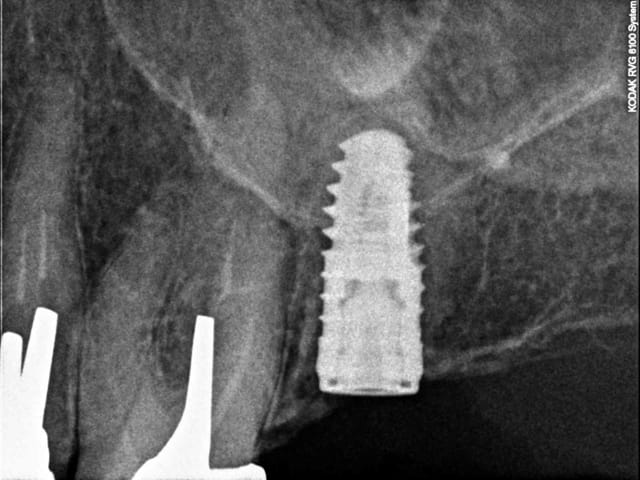

J'ai complètement foiré la pose d'un implant (46)en l'angulant d'une fort mauvaise façon directement au contact de la racine de la dent de devant (45)enfin c'est ce que me montre la radio.....j essaierai de la poster plus tard.

Justement par rapport à ton cas la question qui me semble essentielle est : Pourras-tu réaliser la prothèse correctement si ton implant est si mésialé ???

Si c'est pas le cas autant enlever l'implant à 2-3 semaines quand la stabilité primaire est faible en expliquant la chose au patient.

Tiens là aussi contact avec la racine de 26.

Rattrapage aprés retrait et réinsertion de l'implant.

Il ne faut pas non plus oublier qu'une radio n'est qu'une image en 2D, ce qui peut donner l'illusion qu'un implant est au contact de la dent voisine, alors qu'il n'en est rien. D'autant plus que la racine d'une dent naturelle est très proche de la table externe, alors l'axe d'un implant sera plutot centré dans la masse osseuse de la crête.